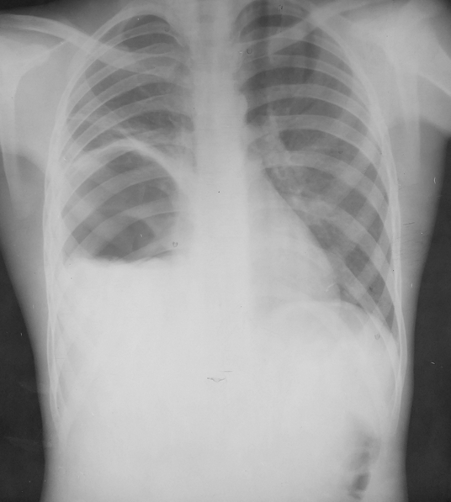

Rx toracică, incidență P-A

DESCRIERE:

la niv. întregului hemitorace drept → opacitate extinsă, nesistematizată, de intensitate mare, omogenă

caracter expansiv → împinge traheea și mediastinul de partea opusă

diafragm deplasat în jos

lărgirea spațiilor intercostale

umplerea spațiului costo-diafragmatic

DX: pleurezie masivă

DD: atelectazie → caracter retractil